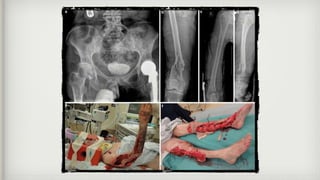

What do they look like on X-

ray?

What do theylook like on X- ray?